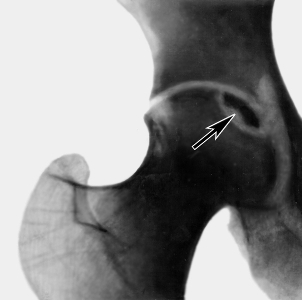

Для уточнения диагноза могут быть использованы такие методы диагностики, как МРТ или рентгенография. При этом остеонекроз можно предполагать в том случае, когда при переломе есть болевые ощущения, которые со временем не проходят, а только усиливаются, а также при болях в тазобедренном суставе, если известно, что человек до этого длительное время — год и более, принимал большие дозы гормональных препаратов.

Если рентгенография не может выявить пораженные участки, то понадобится другое, более точное диагностическое исследование – МРТ. Также нужно помнить, что проводится исследование двух суставов, так как это заболевание имеет особенность – оно поражает одновременно обе ноги человека.

Что же касается сцинтиграфии, то она не способна дать полную картину патологии, поэтому используется только в самых крайних случаях.